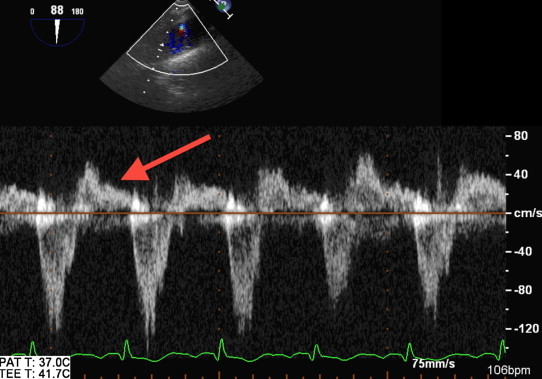

A transthoracic echocardiogram showed severe aortic regurgitation with decreased left ventricular ejection fraction of 40%. A subsequent transesophageal echocardiogram demonstrated a mobile echodensity on the non-coronary cusp of the aortic valve prolapsing into the left ventricle outflow tract (Fig. 1). There was severe aortic valve regurgitation associated with holodiastolic flow reversal in the descending thoracic aorta (Fig. 2). The echocardiographic findings along with the patient's blood culture results are consistent with aortic valve endocarditis.

Fig. 2.

Spectral Doppler image showing (arrow) holodiastolic flow reversal in the descending thoracic aorta consistent with severe aortic insufficiency.